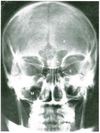

Label this.

What are the sutures of the skull and what are the joining points you need to know?

What suture is this?

Coronal suture

Sagittal suture

Lambdoid suture (parieto-occipital suture)